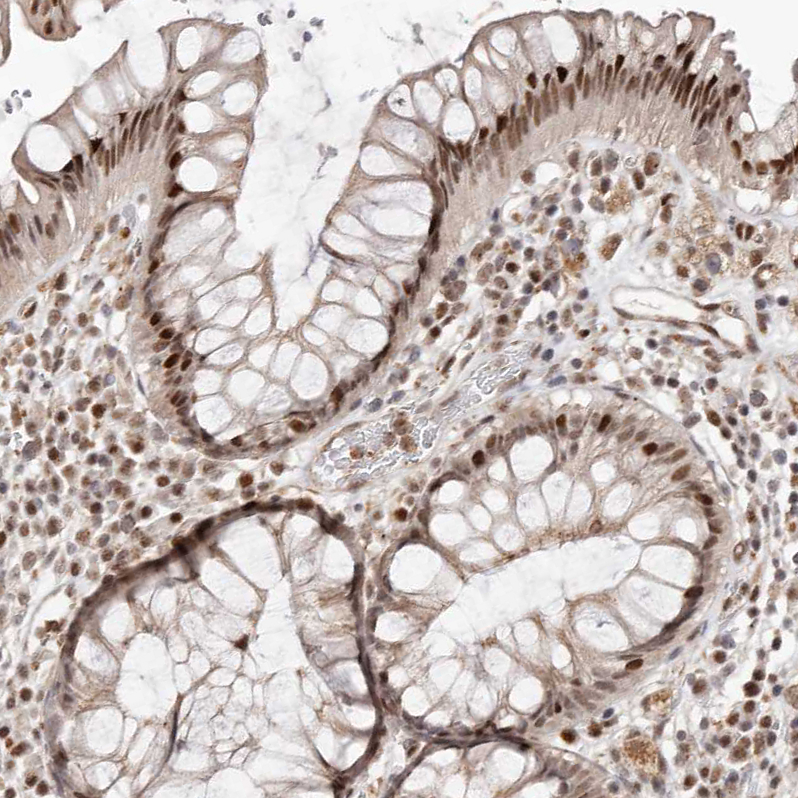

Immunohistochemical staining of human lung shows strong cytoplasmic-nucleus positivity in macrophages.